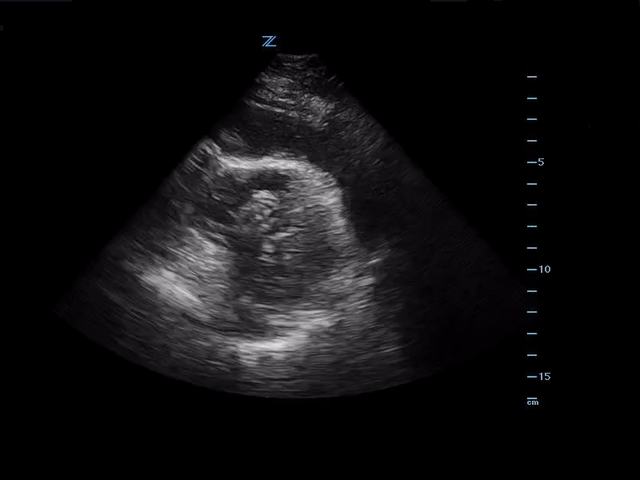

Bedside ultrasound showed the following:

Large pericardial effusion with evidence of RV free wall collapse. PSL view.